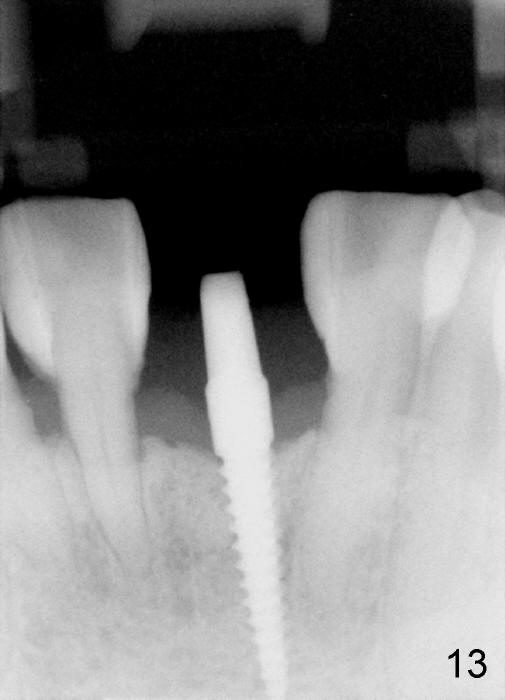

Fig.10,11 show 7 day follow up.  The permanent crown is seated 4.5 months postop (Fig.12).  Minimal bone resorption occurs at the crest 4 months postop (Fig.13), which is most likely associated with conservative approach (flapless).  The patient returns for follow up 2.5 months post cementation (Fig.14,15).  The implant remains in the bone 4 years post cementation (Fig.16 CT coronal section; lingual thread exposure, corresponding to preop defect in Fig.1).   There is mild coronal bone resorption 5 years 4 months post cementation (Fig.17).